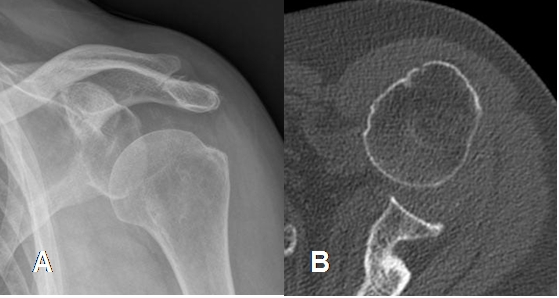

Fig 46. Subluxación anterior.

A: Rx AP y B: TAC axial. Desalineación anterior de la articulación glenohumeral, con pérdida parcial de la relación articular.